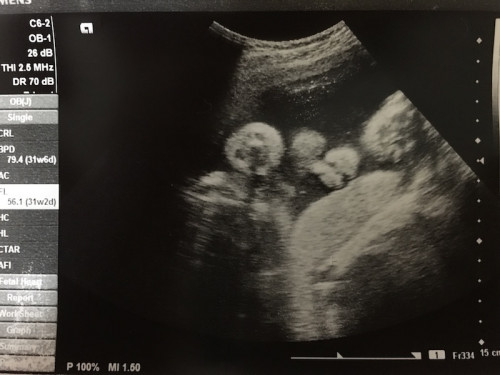

超音波診写真(通称エコー写真)は、かたいものに当たると反射する超音波の性質を利用し、赤ちゃんの体の断面を映し出したものです。骨などの硬いものは白く、羊水などの液体は黒く写ります。

産院の先生はよく、頭の横幅、大腿骨の長さ、お腹を輪切りにしたような映像を見せてくれると思うのですが、それは推定体重を出すのに必要な値だからです。

上写真は30週の時のもので、顔がこちらを向いている写真。鼻の形や鼻の穴、口、頬などが確認できます。